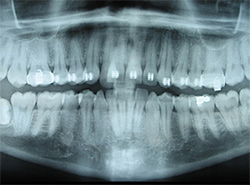

Digital X-Rays

x-rayUsing the most advanced dental technology possible is just as important as staying up-to-date on the latest treatment techniques. Because our practice is dedicated to providing you with the safest and most convenient treatment options available, we utilize advanced digital X-ray technology in our office.

Digital X-rays provide several advanced imaging options, designed to save time, provide clearer dental photos, and expose patients to less radiation than with traditional X-ray technology.

Our practice is focused on making your dental experience as comfortable as possible. At your next appointment, we’ll be happy to answer any questions you may have.